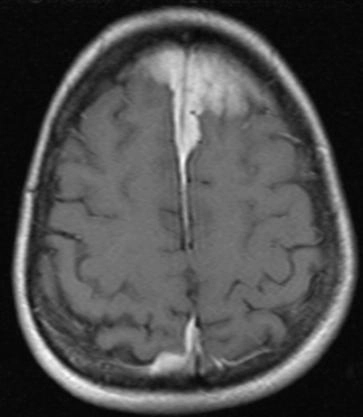

• Dày hộp sọ (Calvarial thickening)